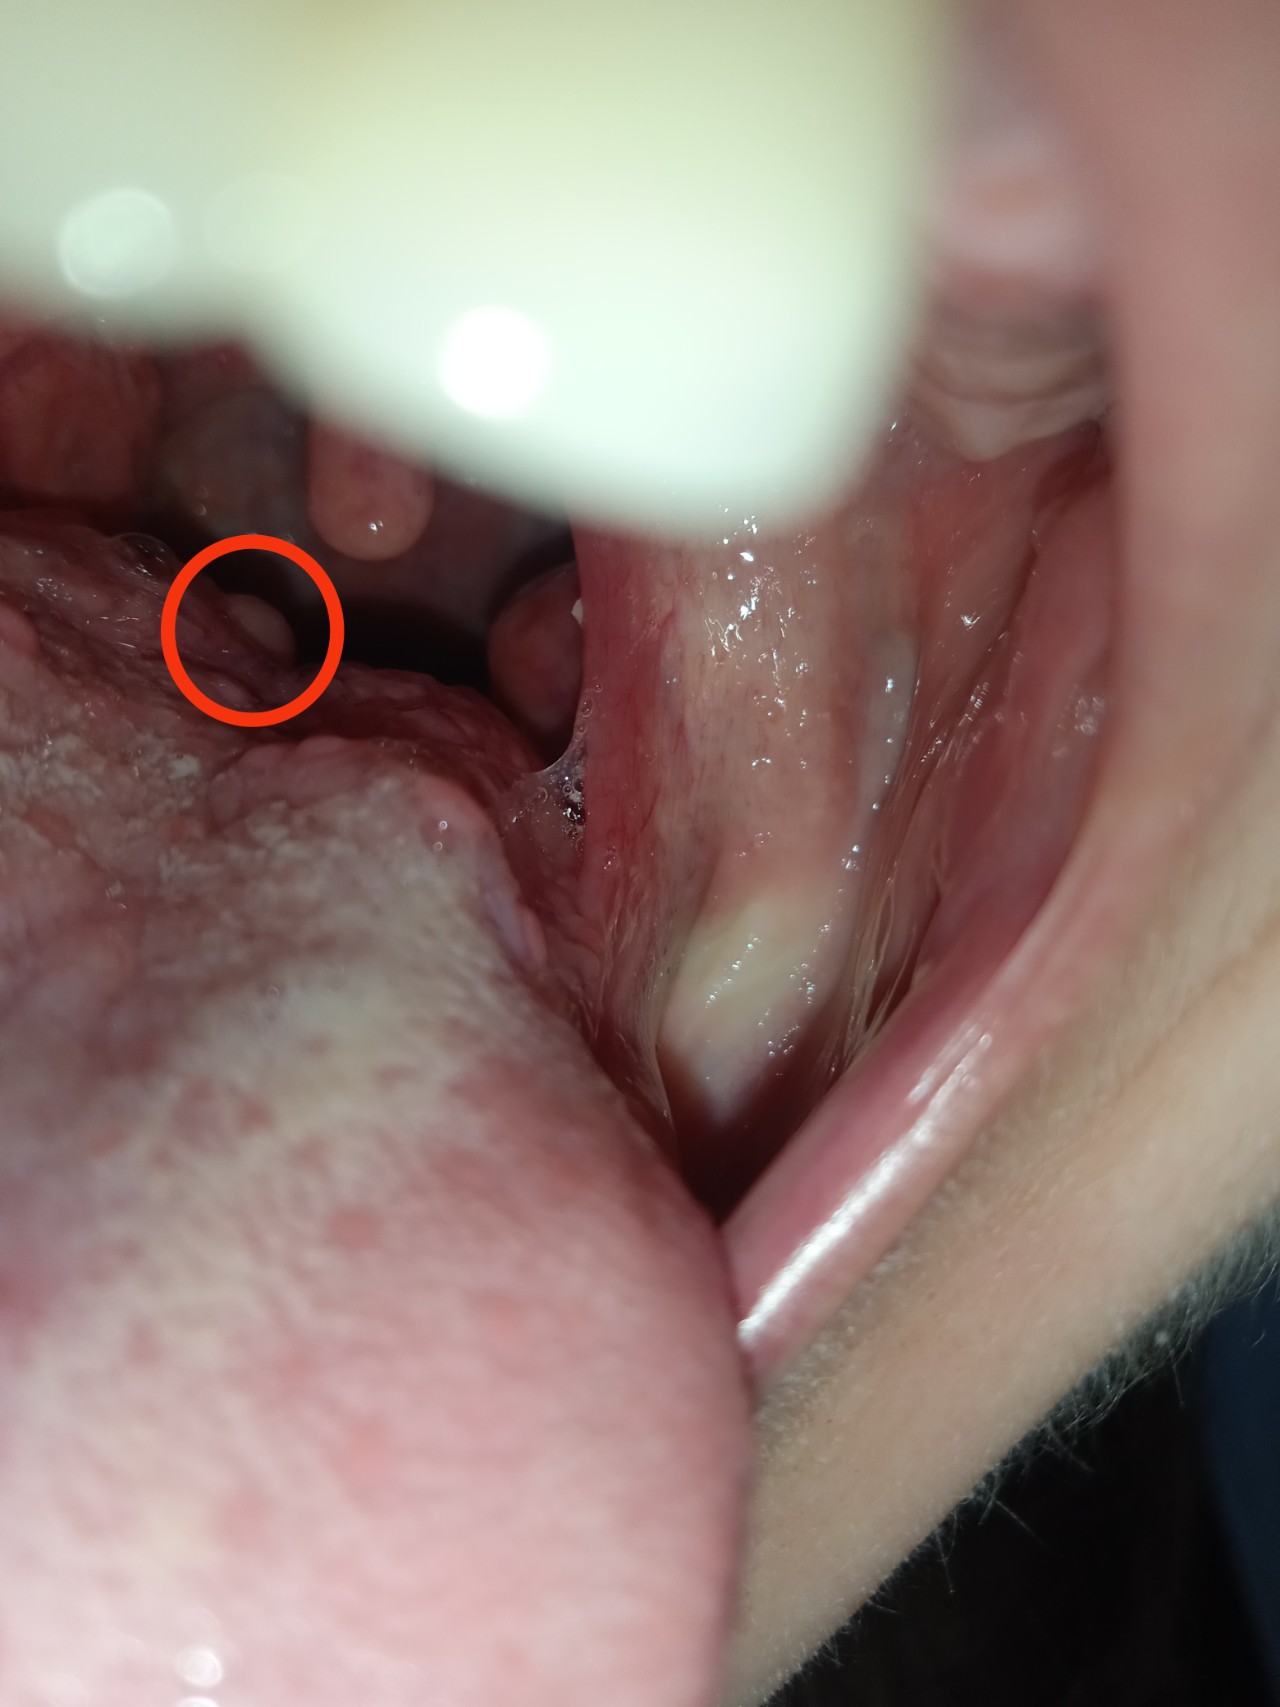

В вівторок випадково знайшла утворення на корені язика. Роздивитися і взагалі помітити його важко. На фото обвела червоним кільцем. В середу вже було важче говорити.

Була в сімейного лікаря, та направила до ЛОРа, сама не змогла роздивитися утворення. В ЛОРа була вчора, лікар направила до ЛОРа-онколога, теоретичний діагноз - папілома, 0.5 мм. Огляд лором-онкологом аж у понеділок, але зараз мене дуже болить шия там, де всередині з правої сторони знаходиться це утворення, часом охрипаю, напружувати горло і довго говорити не можу.